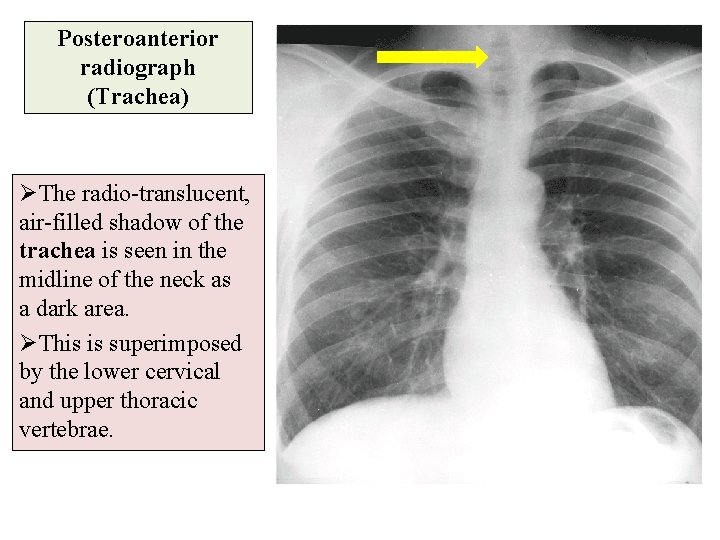

Posteroanterior radiograph (Trachea) ØThe radio-translucent, air-filled shadow of the trachea is seen in the midline of the neck as a dark area. ØThis is superimposed by the lower cervical and upper thoracic vertebrae.